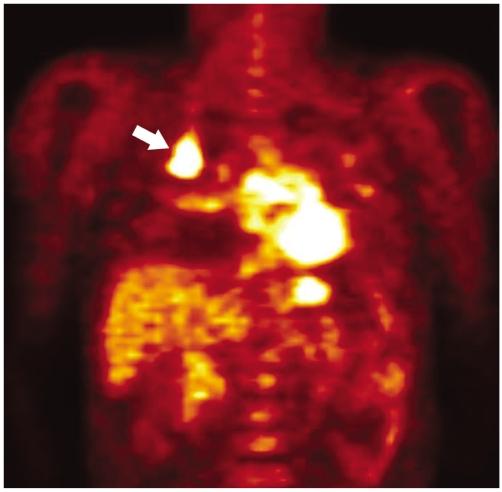

Fluorodeoxyglucose (FDG)-positron emission tomography (PET) is being used more and more to differentiate benign from malignant focal lesions and it has been shown to be more efficacious than conventional chest computed tomography (CT). However, FDG is not a cancer-specific agent, and false positive findings in benign diseases have been reported. Infectious diseases (mycobacterial, fungal, bacterial infection), sarcoidosis, radiation pneumonitis and post-operative surgical conditions have shown intense uptake on PET scan. On the other hand, tumors with low glycolytic activity such as adenomas, bronchioloalveolar carcinomas, carcinoid tumors, low grade lymphomas and small sized tumors have revealed false negative findings on PET scan. Furthermore, in diseases located near the physiologic uptake sites (heart, bladder, kidney, and liver), FDG-PET should be complemented with other imaging modalities to confirm results and to minimize false negative findings. Familiarity with these false positive and negative findings will help radiologists interpret PET scans more accurately and also will help to determine the significance of the findings. In this review, we illustrate false positive and negative findings of PET scan in a variety of diseases.